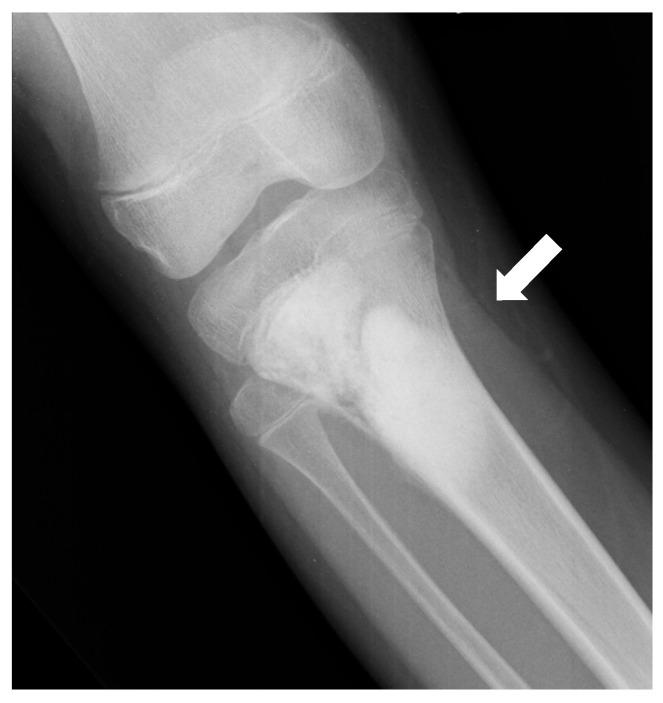

Osteosarcomas are rare malignancies (<1% of all cancers) that produce an osteoid matrix. Osteosarcomas are the second most frequent type of primary bone tumor after multiple myeloma and the most prevalent primary bone tumor in children. The spectrum of imaging findings of these malignancies varies significantly, reflecting different histological subtypes. For instance, conventional osteosarcoma typically presents with a mixed radiological pattern (lytic and bone mineralization) or with a completely eburneous one; aggressive periosteal reactions such as sunburst, Codman triangle, and soft-tissue components are frequently displayed. On the other hand, telangiectatic osteosarcoma usually presents as a purely lytic lesion with multiple fluid-fluid levels on MRI fluid-sensitive sequences. Other typical and atypical radiological patterns of presentation in other subtypes of osteosarcomas are described in this review. In addition to the characteristics associated with osteosarcoma subtyping, this review article also focuses on imaging features that have been associated with patient outcomes, namely response to chemotherapy and event-free and overall survivals. This includes simple semantic radiological features (such as tumor dimensions, anatomical location with difficulty of radical surgery, occurrence of pathological fractures, and presence of distant metastases), but also quantitative imaging parameters from diffusion-weighted imaging, dynamic contrast-enhanced MRI, and 18F-FDG positron emission tomography and radiomics approaches. Other particular features are described in the text. Overall, this comprehensive literature review aims to be a practical tool for oncologists, pathologists, surgeons, and radiologists involved in these patients' care.

骨肉瘤是一种罕见的恶性肿瘤(占所有癌症的比例不到1%),可产生类骨质基质。骨肉瘤是继多发性骨髓瘤之后第二常见的原发性骨肿瘤类型,也是儿童中最常见的原发性骨肿瘤。这些恶性肿瘤的影像学表现谱差异很大,反映了不同的组织学亚型。例如,传统骨肉瘤通常表现为混合性放射学模式(溶骨性和骨矿化)或完全骨化模式;常显示侵袭性骨膜反应,如日光放射状、科德曼三角和软组织成分。另一方面,毛细血管扩张性骨肉瘤通常表现为纯溶骨性病变,在MRI液体敏感序列上有多个液-液平面。本文综述了骨肉瘤其他亚型的其他典型和非典型放射学表现模式。除了与骨肉瘤亚型相关的特征外,本文还重点关注与患者预后相关的影像学特征,即对化疗的反应、无事件生存期和总生存期。这包括简单的语义放射学特征(如肿瘤大小、根治性手术困难的解剖位置、病理性骨折的发生以及远处转移的存在),也包括扩散加权成像、动态对比增强MRI、18F-FDG正电子发射断层扫描和放射组学方法的定量成像参数。文中还描述了其他特殊特征。总体而言,这篇全面的文献综述旨在成为参与这些患者护理的肿瘤学家、病理学家、外科医生和放射科医生的实用工具。